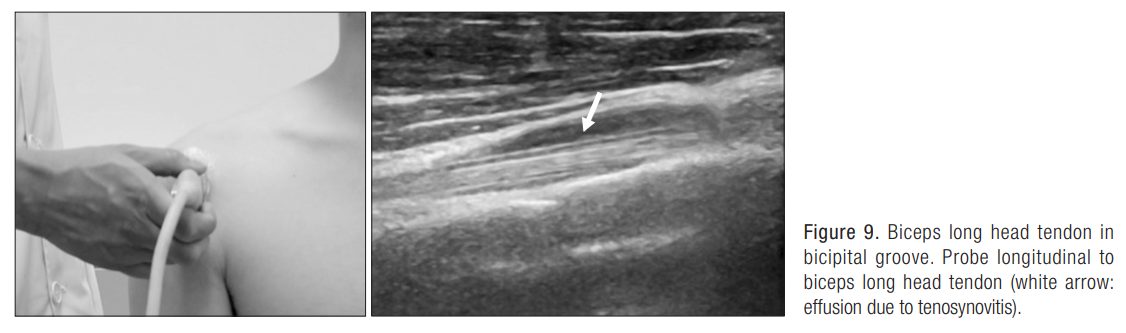

5. 이두박건 주사(Biceps long head tenosynovitis injection)

이두박건 장두부는 극상건과 견갑하건 사이에 위치, 회전근개 간격(Rotator interval)에 위치, 관절 내 상부

이두박근의 장두부는 상완골의 도랑을 지나가는데, 이 부위에서 손상시 극심한 통증 유발

이두박건이 신전되는 자세인 견관절의 신전 및 외전 자세에서 통증이 유발됨.

건초염이 있을 때에는 건막의 effusion을 확인할 수 있다.

1) 처음에는 longitudinal하게 needling 시행

Needle의 끝이 이두박건의 sheath를 뚫어, sheath와 건 사이에 needle을 위치

위치 확인 후 주사액 주입

2) transverse하게 탐촉자를 변경시키고, 주사액이 잘 들어감을 확인

견관절을 out-stretching 시 통증이 유발되면서, 초음파 상에서 effusion 있을 때, 주사 치료를 고려

극상건 혹은 극하건 파열의 증식치료와 병합(회전 근개 파열에서 이두장건의 건초염 동반 시)

관절와상완 관절 내 주사 치료 시에는 이두장건 건초로 약물이 퍼지기 때문에 병합 치료는 하지 않아도 된다.